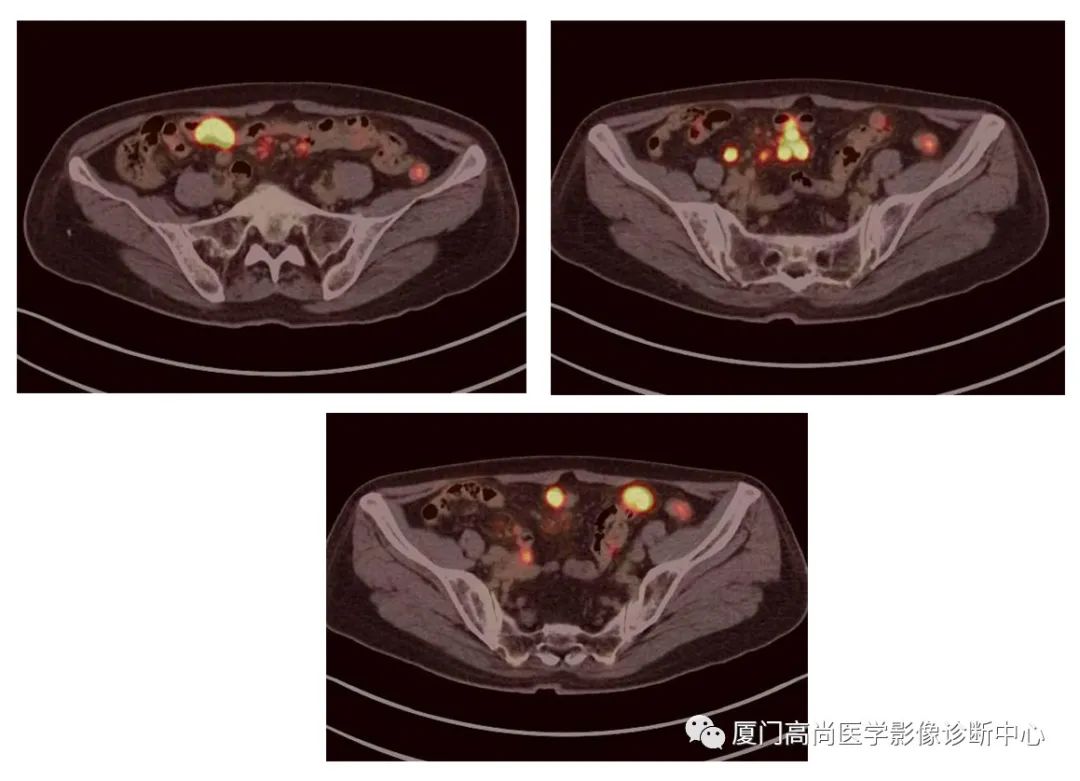

腹腔淋巴結(jié)腫大

小腸多段淋巴瘤病灶

PET/CT發(fā)現(xiàn) :左心房、右心房見團塊狀FDG攝取增高;雙側(cè)腎上腺增大,F(xiàn)DG攝取增高;膽囊和胃壁結(jié)節(jié)樣FDG攝取增高;小腸多節(jié)段腸壁增厚,F(xiàn)DG攝取增高;腹膜后、腹腔及盆腔多發(fā)淋巴結(jié)腫大,F(xiàn)DG攝取增高;上述考慮為淋巴瘤

經(jīng)腎上腺穿刺活檢 :病理證實為彌漫大B細(xì)胞淋巴瘤